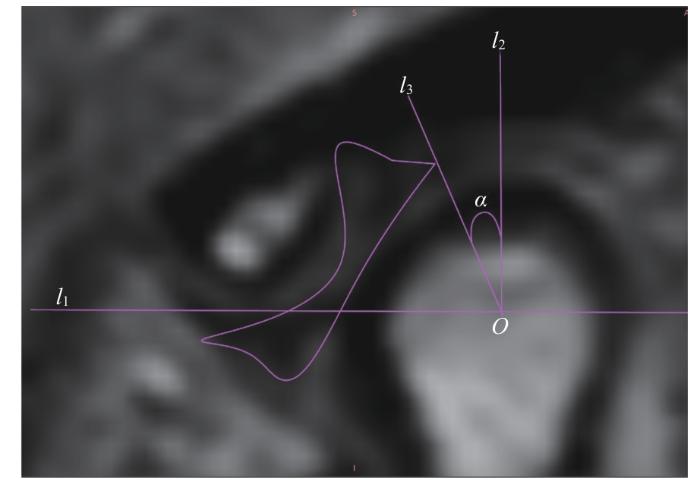

图3

图3   关节盘移位角度的测量

Note: An oblique sagittal PDWI image. l1—the line connecting the articular eminence and the vertex of the posterior tubercle; O—the midpoint of the intersection of line l1 with the condyle; l2—the perpendicular line to l1 through point O; l3—the line connecting the posterior edge of the articular disc with point O; α—the angle between l2 and l3, which is the angle of disc displacement.

Fig 3   Measurement of articular disc displacement angle